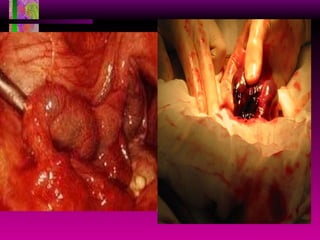

Mola Hidatidiforme Placenta   anormal no invasiva caracterizada por vellosidades coriónicas agrandadas, edematosas y vesiculares acompañada de cantidad variable de trofoblasto proliferativo. Se divide en mola completa (75%) y parcial (25%).

MOLA HIDATIDIFORME